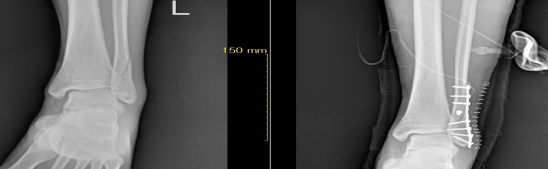

골절 및 탈구시에는 일반 방사선 촬영으로 확진하며 단순골절과 탈구의 경우에는 비수술적 치료방법으로 골절부위를 도수정복 후 석고 고정으로 치유할 수 있습니다. 그러나 도수정복 후에도 골절 부위가 이탈시 부전유합으로 진행되어 추후 어린이는 성장장애 및 외상 후 관절증을 유발시켜 장해에 이르기에 부득이 수술적 방법을 고려합니다. 본원은 최신식 이동형 C-ARM 영상장치를 이용하여 골절부위를 실시간으로 촬영하여 수술을 시행하고 있습니다.